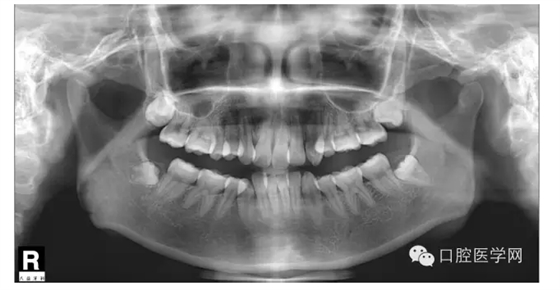

這是一位我同事接診的一位患者,成年女性,安氏II類,高角,下頜后縮,重度深覆合,上下中線右偏,原本做過一次矯正,4個4已經(jīng)拔除。

我同事又給她拔了左邊兩個5,然后我同事離職了,把患者扔給我。

所以這個患者我選擇使用弓絲壓低下前牙。但由于雙尖牙只剩下15,45,所以我們將37,47,納入矯正。